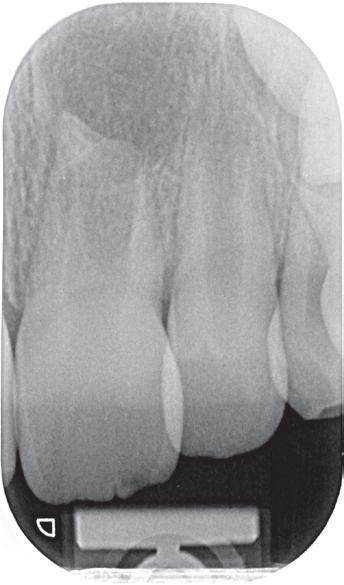

Voordat je aan een wortelkanaalbehandeling begint, zorg je voor (of maak je) een goede beginfoto waar het te behandelen gebitselement volledig op staat afgebeeld. Deze foto geeft essentiële informatie: de grootte van de pulpakamer en de ligging ervan; het aantal en de vorm van de wortels en de breedte van hun wortelkanalen en de lengte van de wortels. Hiermee kan je de DETI-score bepalen en de moeilijkheidsgraad inschatten. De grootte en de ligging van de pulpakamer op de röntgenfoto in combinatie met de ideale anatomische vorm, zoals in foto 1 is aangegeven, bepaalt de uiteindelijke vormgeving van de opening. Bij de molaren liggen de kanaalingangen in de buurt van de knobbeltoppen. Als die niet meer in originele staat

De verwijzend tandarts is bezig om een wortelkanaalbehandeling uit te voeren in gebitselement 27. Er zijn vier kanalen gevonden, maar helaas breekt er in het mesiobuccale kanaal (MB 1) een WaveOne vijltje af, maat geel (foto 2). Het lukt de tandarts niet om

2. Het afgebroken instrument op de foto van de verwijzend tandarts.

3. De opening is vrij klein gekozen. In rood is de ideale opening aangegeven, de tandarts had veel meer restauratiemateriaal mogen wegnemen.

Als ik de patiënte zie, valt me op dat de opening die de tandarts gemaakt heeft, nogal klein is (foto 3). Eigenlijk is daar niet zoveel reden toe; als ik een ideale opening inteken (in rood), dan loopt een groot deel door restauratiemateriaal. Overwogen kan worden om de aanwezige mesiale box met restauratiemateriaal weg te halen als dat het zicht op de pulpakamer vergroot – ik verwijs naar de tip hierboven (wees bij het openen niet spaarzaam met het wegnemen van aanwezig restauratiemateriaal).